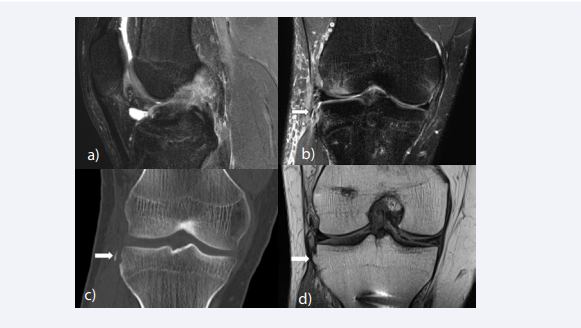

A Segond fracture is an avulsion fractures located at the lateral rim of the tibia, pathognomonic for an ACL tear [64,65] (Figure 4).

Segond fracture and Bosch-Bock bump. (A) Sagittal fat-suppressed T2-weighted image shows a complete tear of the ACL. (B) On coronal fat-suppressed T2- weighted image, a small avulsed bone fragment (white arrow) is noted at the lateral rim of the tibia (Segond fracture), which is a finding pathognomonic for an ACL  tear. (C) Corresponding CT images clearly depicts the Segond fracture. (D) The patient underwent ACL reconstruction surgery and on postoperative follow-up MRI  taken 2 years after the injury, the Segond fracture has healed, creating a characteristic bone excrescence at the lateral aspect of the proximal tibia (“Bosch-Bock bump”).

Figure 4 :Segond fracture and Bosch-Bock bump. (A) Sagittal fat-suppressed T2-weighted image shows a complete tear of the ACL. (B) On coronal fat-suppressed T2- weighted image, a small avulsed bone fragment (white arrow) is noted at the lateral rim of the tibia (Segond fracture), which is a finding pathognomonic for an ACL tear. (C) Corresponding CT images clearly depicts the Segond fracture. (D) The patient underwent ACL reconstruction surgery and on postoperative follow-up MRI taken 2 years after the injury, the Segond fracture has healed, creating a characteristic bone excrescence at the lateral aspect of the proximal tibia (“Bosch-Bock bump”).

Segond fractures occur from forced internal rotation and varus loading of the tibia relative to the femur [64,66]. They have been attributed to various structures; the mid-third lateral capsular ligament, the iliotibial band, the anterior arm of the biceps femoris tendon, the anterolateral ligament, and the anterolateral complex consisting of the ITB and anterolateral capsule [66-72]. Segond fracture has a reported prevalence of 2.4% to 29% in patients with ACL tears [64,65,73,74]. The healing of a Segond fracture may lead to a characteristic bone excrescence at the lateral aspect of the proximal tibia (“BoschBock bump”) [73] (Figure 4D).